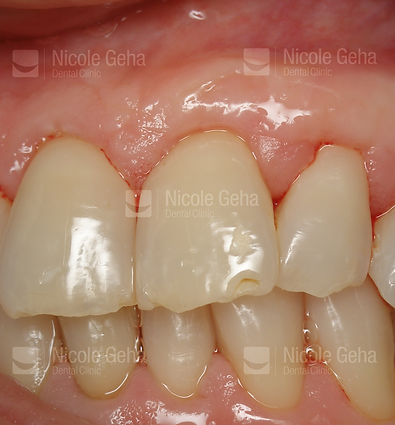

case 2: before replacing the bridge

case 2: after implant placement